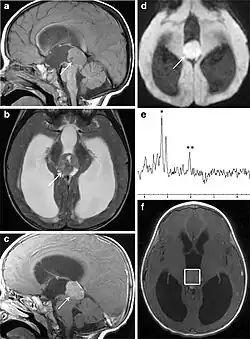

Several imaging methods can be used to diagnose pineoblastoma. Initially, urgent CTs are recommended, followed by MR imaging.[13] CT will show large, multilobulated masses with heterogenous contrast enhancement and peripheral calcification of the pineal gland.[4][3] On MRI, pineoblastomas again appear as masses with heterogenous enhancement. They often appear hypo- to isointense on T1 and slightly hyperintense on T2-weighted images. Some areas of necrosis or hemorrhage may be seen as well. PET-CT has also been used in diagnosis, and shows increased uptake of fludeoxyglucose with pineoblastomas compared to other pineal masses.